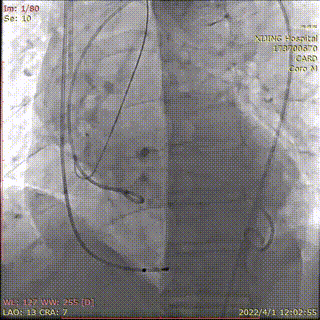

术中DSA影像:

术前造影并测压,显示AS+AR

左冠预埋球囊行冠脉保护

25mm球囊预扩张,有腰征,无漏

应用可调完系统顺利过弓

左右窦重合角度造影定位

右窦居中角度造影定位

多角度透视影像下显示可调弯输送器系统能保障瓣膜释放时与主动脉根部的同轴性。

释放26mmPrizValve,瓣架有腰征

术后造影微量PVL,瓣架形态位置理想

术后主动脉瓣上血压174/64(101),左心室血压187/22(77),最大跨瓣压差13mmHg。考虑球囊后扩张对左冠有影响,撤出左冠内球囊,手术结束。